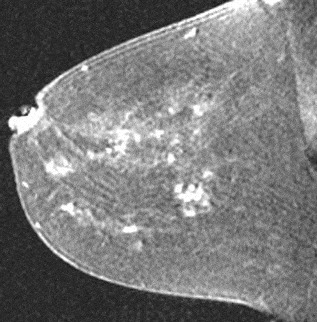

A focus is a tiny punctate enhancement that is non-specific and too small to be characterized. A focus is clearly not a space-occupying lesion or mass and is smaller than 5 mm (Fig. 1).

Figure 1. Non-specific foci of enhancement – unchanged on follow-up scans.